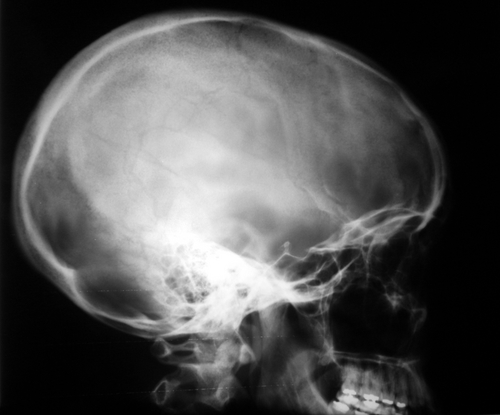

A new study by researchers at the University of Tennessee, Knoxville, found that some Americans' heads have grown larger over the past two centuries.

Forensic anthropologists at the university studied 1,500 skulls dating back to the mid-1800s to the mid-1980s. The researchers found that caucasian American skulls have grown larger, taller and more narrow as time has passed. Caucasian American faces have also become significantly higher and more narrow, according to the university.

The average height of the skull has increased by nearly one-third of an inch, and skull size has grown by 200 cubic centimeters in men and 180 cubic centimeters in women — about the size of a tennis ball.

The increase in skull height is not proportional to other increases in American body size. Skull height has increased by 6.8 percent since the late 19th century and continues to increase. Body height has increased by 5.6 percent in the same time period, while femur length has increased by only 2 percent. Both body height and femur length changes have slowed or stopped in recent years, though.

The team also found evidence of Americans maturing earlier in life. A separation in the bone structure of the skull was once thought to close at about age 20. In the skulls studied, the gap had fused at age 14 for females and at age 16 for males.